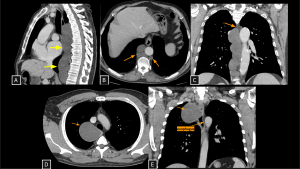

Fig 8: Cases 8 and 9 – Malignant neural-lineage neoplasm presenting as a visceral mediastinal mass and Neurofibromas.

A 21-year-old patient with a history of neurofibromatosis type 1 undergoing evaluation for cough and constitutional symptoms. Chest radiograph (A) showed mediastinal widening and a left pulmonary mass. Corresponding to the radiographic findings, contrast-enhanced chest CT (B and C) demonstrated two heterogeneous expansile lesions located in the visceral mediastinum and left thoracic wall, containing hypoattenuating foci (likely cystic components). Biopsy of the right paratracheal lesion revealed a malignant peripheral nerve sheath tumor.

Case 9 (D–F) demonstrates disseminated plexiform neurofibromas: a neck mass splaying carotid space vessels without stenosis (D), multiple fusiform hypoattenuating intercostal lesions (E), and extensive retroperitoneal soft tissue encasing the aorta and celiac trunk (F).

MPNST (Malignant Peripheral Nerve Sheath Tumor) SYSTEMATIC APPROACH: 1. Age: Adults (increased risk in NF1). | 2. Morphology: Large, ill-defined mass with necrosis/hemorrhage. | 3. Enhancement: Heterogeneous/Peripheral. | 4. Relevant Anatomical Relationships: Invasive; rapid growth with destruction of adjacent planes.

Neurofibroma SYSTEMATIC APPROACH: 1. Age: Pediatric/Young Adults (NF1 context). | 2. Morphology: Diffuse, infiltrative ("Bag of worms"). | 3. Enhancement: Variable. | 4. Relevant Anatomical Relationships: Multicompartmental; involves nerve plexuses/branches.